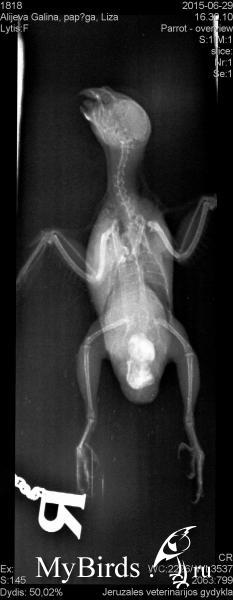

galiuniaaa Опубликовано 29 июня, 2015 Автор #12 Опубликовано 29 июня, 2015 (изменено) Снимкиврча адекватный попался. сказал такого не видел и не может понять что за соединение между ними. Это яйца?? Изменено 29 июня, 2015 пользователем galiuniaaa

Zosia Опубликовано 29 июня, 2015 #14 Опубликовано 29 июня, 2015 galiuniaaa, постучите в личку Зосе. На моей памяти- ВТОРОЙ случай ЖИВОЙ двухяйцевой самки... все написала в личке.

galiuniaaa Опубликовано 29 июня, 2015 Автор #15 Опубликовано 29 июня, 2015 На моей памяти- ВТОРОЙ случай ЖИВОЙ двухяйцевой самки... все написала в личке. Спасибо большое !!Теперь нам нужен пряморукий врач...

Delfin Опубликовано 29 июня, 2015 #16 Опубликовано 29 июня, 2015 (изменено) а вы еще рентген не хотели делать! Я в ШОКЕ сижу...не думала что ТАКОЕ бывает... ожидала всего что угодно, но ТАКОГО... Галина, вечно у вас как то все... странно.Но ЖЕЛАЮ ВСЕГО НАИЛУЧШЕГО!!!держитесь! и хорошего вам ВРАЧА! Изменено 29 июня, 2015 пользователем Delfin

galiuniaaa Опубликовано 29 июня, 2015 Автор #17 Опубликовано 29 июня, 2015 а вы еще рентген не хотели делать! Я в ШОКЕ сижу...не думала что ТАКОЕ бывает... ожидала всего что угодно, но ТАКОГО... Галина, вечно у вас как то все... странно.Но ЖЕЛАЮ ВСЕГО НАИЛУЧШЕГО!!!держитесь! и хорошего вам ВРАЧА! Не говори...Я сама сижу в шоке..Я ожидала чего угодно но чтоб 2 !!! Надеюсь после долгих мазаний и паровой ванны она разродится сегодня, хоть одно чтоб вышло...Ждем до утра и сразу в вет. могли сегодна пробовать но я хотела услышать Зоси вердикт... Вет.врач сказал яйца и неординарный случай но он в сомнениях был насчет этого соединения,как такое может быть.Он фото отправил коллегам, но мы завтра летим в клинику и по инструкции Зоси будем все пытаться достать.... Пожелайте нам удачи, сейчас нам она нужна благо птица держится и ведет себя как обычно ,после сильнейшего стресса перенесенного в клинике..

Zosia Опубликовано 30 июня, 2015 #38 Опубликовано 30 июня, 2015 У меня сомнения в том что нет скорлупы, как такое может быть и что делать? ( Надеюсь Зося скажет как такое может быть...Жидкость идет а скорлупки нет Я подозреваю,что ОБА яйца были с мягкой (малокальцинированной) скорлупой. Только так я могу объяснить появление двух яичек сразу в яйцеводе. Т.е появилось первое, из-за мягкости нет достаточного давления на сленки яйцевода,соответственно- нет нужного сигнала на ПСН, и нет достаточной "родовой деятельнсоти". Через 36 часов выходит следующее яичко,продвигается дальше,упирается в первое- и получаете вашу ситуацию. Из-за мускульных сокращений ("схваток") яйца раздавливаются, давление опять падает,родовая деятельность прекращается.Как-то так мне видится механика вашего случая...